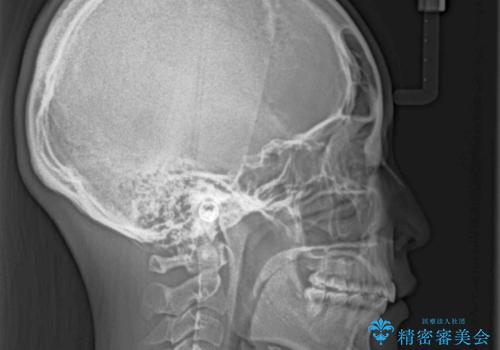

舌の突出癖があり、咬合力も強かったため、治療期間は長くなることが懸念されましたが、舌のトレーニングをしっかりと行っていただいたこともあり、2年弱で治療を終えることができました。